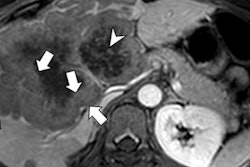

The review of images also found 80 liver metastases in patients. PET/CT correctly identified 68 (85%) of the liver metastases as malignant. Of the remaining malignant lesions, eight lesions were too small to characterize on CT and four lesions were not detected at all. By comparison, PET/MRI again correctly identified all the lesions as malignant.

Correct identification of all malignant neuroendocrine tumor lesions with PET/MRI was possible, while PET/CT "remained inconclusive" in several cases, Beiderwellen concluded. PET/MRI also discovered 12 additional liver metastases not detected by PET/CT.